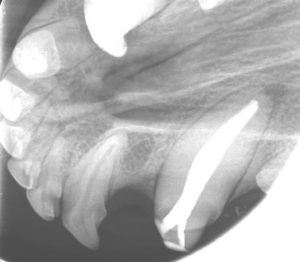

Hoy os contamos el caso de Multik, un perrito de casi 3 años que llegó a IVeM tras sufrir un traumatismo en su canino superior izquierdo. Gracias a un diagnóstico rápido y un tratamiento conservador, conseguimos salvar su diente y devolverle la sonrisa.

Inicialmente, le realizamos una pulpectomía total (endodoncia) para eliminar todo el tejido pulpar, limpiando cuidadosamente el canal. Posteriormente, tomamos impresiones digitales del diente para diseñar una solución a medida. Y finalmente, fabricamos y colocamos una

corona de zirconio, un material altamente resistente, biocompatible y estético. Así, Multik no solo ha recuperado la funcionalidad del diente, sino que también mantiene su sonrisa impecable.